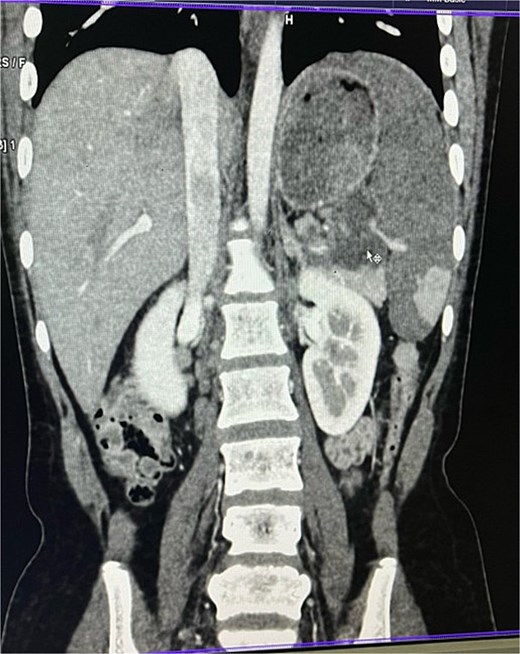

On imaging, ultrasonography showed a lobulated hypoechoic lesion in the region of the pancreatic tail and splenic hilum. This was very not conclusive, so a contrast-enhanced CT scan was planned, which revealed multiple necrotic, conglomerated lymph nodes (30 × 33 × 38 mm) near the splenic hilum and pancreatic tail, abutting the stomach and spleen, with maintained fat planes (Fig. 1). A splenic infarct involving a significant portion of the parenchyma was noted (Fig. 2), with multiple additional necrotic nodes along the retroperitoneum (paraaortic and iliac vessels) and mild pelvic free fluid. Then, CT-guided biopsy from the lymph nodal mass was planned, which showed moderately cellular smears showed caseous necrotic debris, lymphocytes, and clusters of epithelioid cells, suggestive of chronic necrotizing lesion consistent with TB.

Contrast enhanced computer tomography (CECT) abdomen showing necrotic lymph node mass near pancreatic tail and splenic hilum.

CECT abdomen showing splenic infarct involving significant portion of splenic parenchyma—except at the lower pole of spleen.